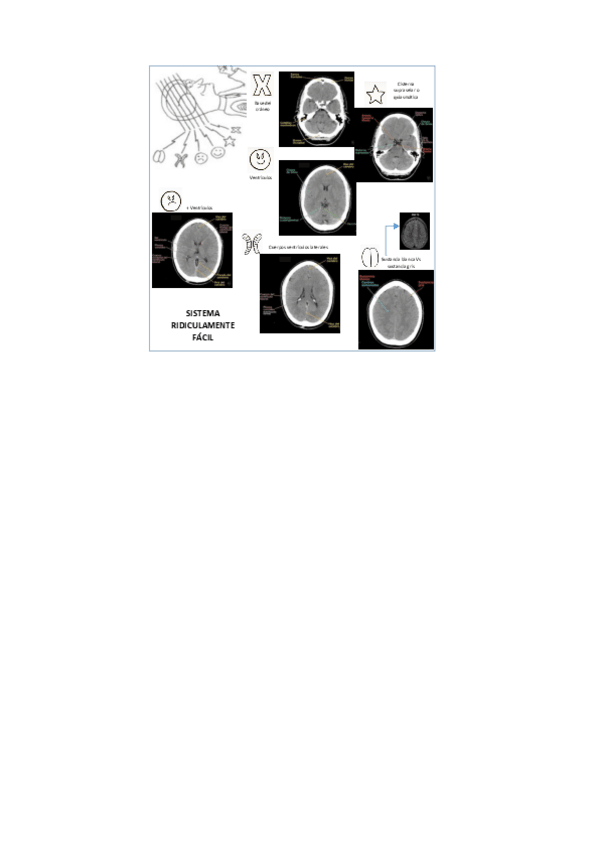

P1.-Protocolos-en-TC-Craneal.pdf